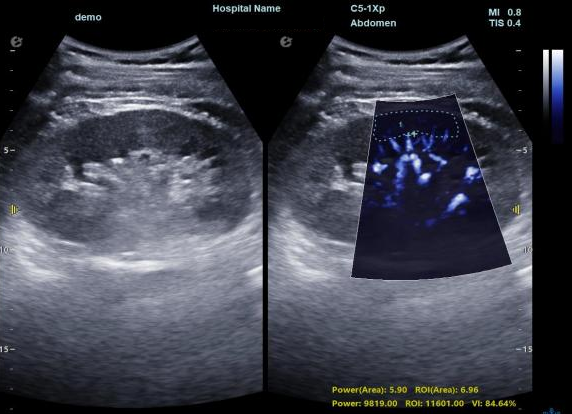

肾脏的灌注评估,RI/VI量化数据

3) 通过血管指数(VI)定量评估局部血管密度,以定量化数据实时监测血流灌注情况,预判肾功能恢复情况;

超微视血流显像评估肾移植术后灌注情况

这一项无创、无辐射操作简便且无需造影剂的黑科技,相当于用"高速摄像机"记录血液细胞的运动轨迹,让血管并发症"无处遁形。

从术前评估到术中到术后,再到终身监护,当20-50μm级的超微血流信号在屏幕上跳动,我们看到的不仅是技术的精进,更是生命的律动。iPlane Vascular正在重新定义肾移植监护的标准——让医生拥有了"显微视力",让每一个微小血管的异常都无所遁形,让每一次免疫排斥的萌芽都被及时扼制。